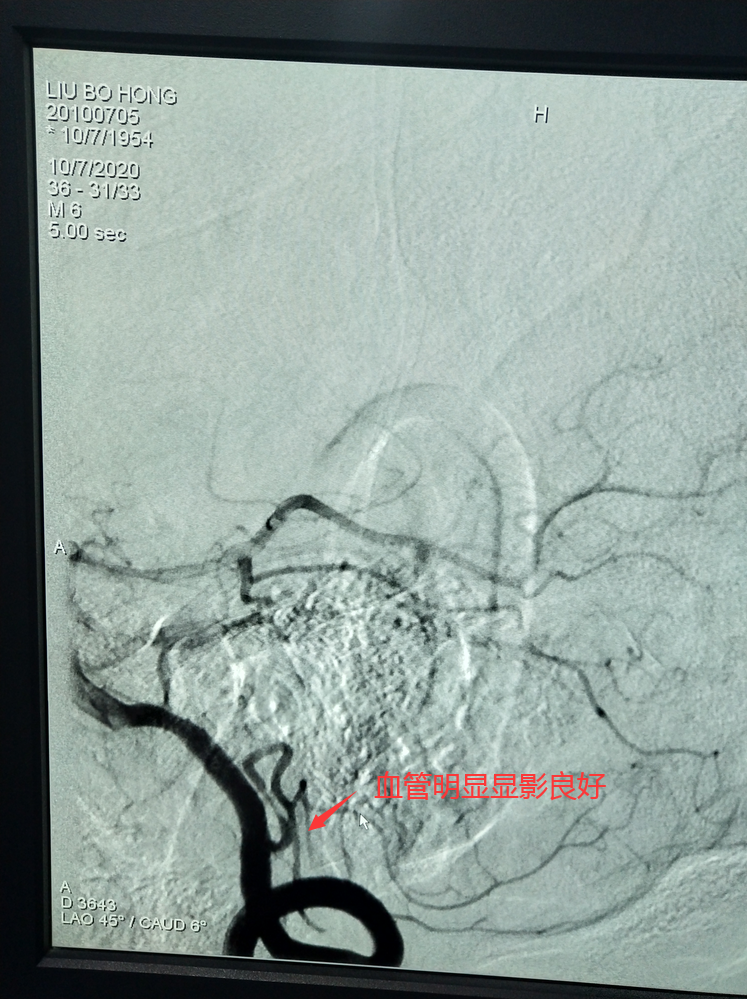

术前造影血管闭塞

血管明显显影良好